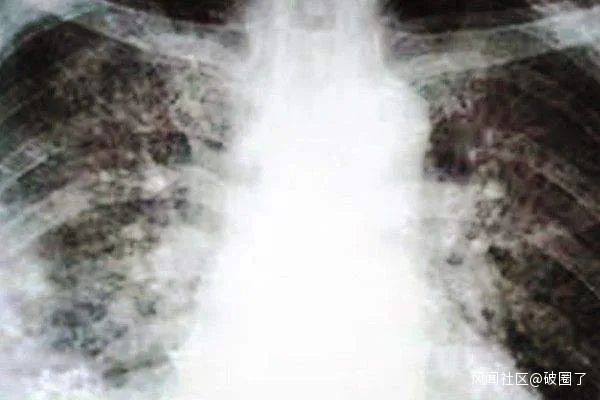

2019年9月7日,英國BBC報道,6月底以來,美國約有200人患上一種神秘的肺病,專家無法確定病因,但懷疑與他們吸食電子煙的習慣有關。隨着新冠肺炎疫情全球蔓延,諸多外媒開始懷疑當時的“電子煙肺炎”是否就是新冠肺炎疫情。2020年3月17日,馬來西亞《詩華日報》報道稱,“根據美國疾控中心資料顯示,僅2019年10月美國境內被確診或疑似感染病例達1080例,遍佈美國48個州,這種病症因在拍攝胸部X光片時呈現一大片的白色狀而被稱為白肺病。當時人們認為此類病症的發生是使用霧化型電子煙,且隨着新冠肺炎疫情暴發,現在許多人開始懷疑美國去年爆發的‘白肺病’可能就是新冠肺炎”。2020年3月11日,美國CDC主任雷德菲爾德稱,“在美國,確實有一些‘流感’死者實際感染的可能就是新冠肺炎”。